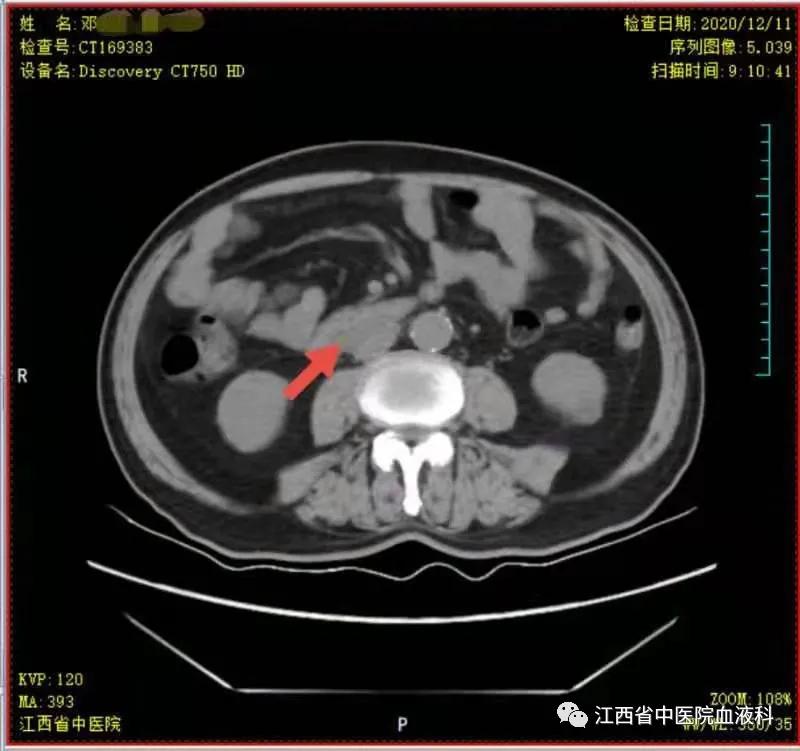

2020年10月中旬邓大爷在家人的陪同下来我科就诊,全腹部增强CT提示:右侧*丸睾**切除术后复查:1.腹膜后(胰头后下方)、双侧肾上腺区团块状异常强化影。2.肝左内叶上段小囊肿,双肾小囊肿,较前相仿。3.右侧腹股沟前方、皮下条索、小片影,境界不清,较前减小,拟为术后改变。4.右下腹腔少许钙化淋巴结,较前相仿。因病情危急,考虑邓大爷高龄、体能差、窦性心动过缓(平均心率50次/分)心脏功能差等情况,经讨论于2020-10-24起第一次行减剂量方案R-miniCHOP(利妥昔单抗700mg d0、环磷酰胺700mg d1、多柔比星40mg d1、长春瑞滨20mg d1、地塞米松10mg d1-5)方案。第一次化疗后评估病情,腹腔瘤体缩小了2/3,取得了很好的治疗效果,可邓大爷心脏却亮起了红灯,经过了积极护心等支持治疗后,大爷心脏功能有所恢复。遂于2020-11-19、2020-12-10行2次R-miniCOP方案(去除了具有心*毒脏**性的多柔比星),三次化疗结束后予评估病情,提示腹腔包块明显缩小,淋巴瘤病情有所好转(见图1至4)。

图3 第二次化疗后瘤块